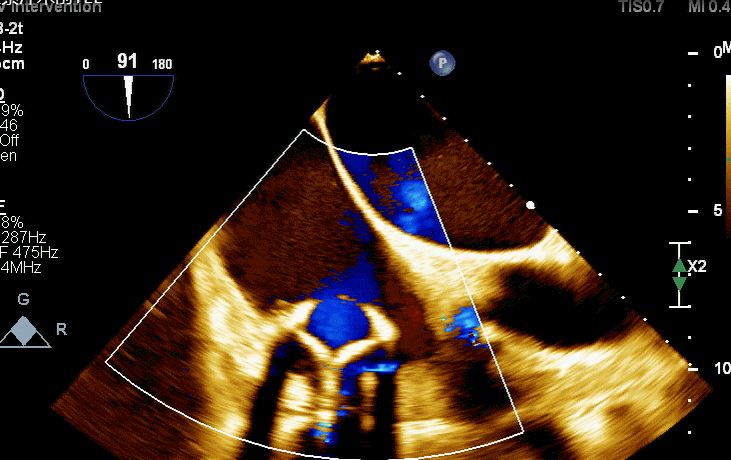

食道超声评估

三尖瓣术前平均压差9mmHg

三尖瓣瓣中瓣术后平均压差3mmHg